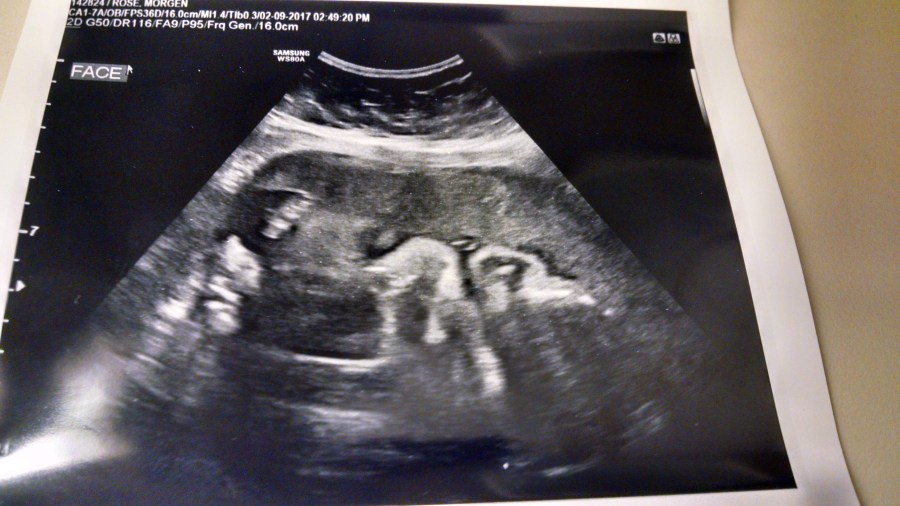

I DID get some new pictures – here’s an ultrasound of her tiny face and hands. Although it’s ever so slightly skeletal and creepy, it’s also pretty cute.

But, of course, it didn’t quite go the way I was hoping. Turns out my fluid is still low and apparently she only weighs 2lbs 7oz, when she “SHOULD” weigh at least 3lbs.